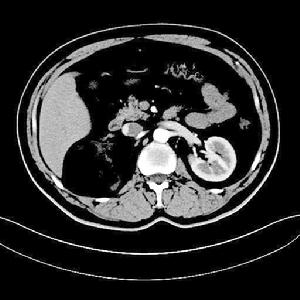

3.CT掃描 CT掃描可精確地確定其大小部位及其周圍關係。

平掃CT可見與腦灰質等密度或稍高密度,松果體區生殖細胞瘤鈣化的幾率較鞍區生殖細胞瘤高得多當松果體區生殖細胞瘤生長過程中有時將鈣化的松果體(呈彈丸狀)包繞在其中故鈣化的“彈丸”可能在瘤內,也可在腫瘤的周邊常在側方或後方偶可被推擠至前方。腫瘤外形呈圓形不規則型或呈蝴蝶形,後者在診斷生殖細胞瘤有著特徵性價值正常人松果體鈣化率約為40%,而有生殖細胞瘤患者的松果體鈣化率近100%;鞍上生殖細胞瘤可無鈣化或細小的鈣化。

增強CT:當CT平掃發現病變的情況下應立即注藥做CT強化掃描表現為中度到明顯的均勻一致的強化少數強化不均勻,可顯示較小的囊變。故兒童或青少年,CT發現有松果體區稍高密度腫物,注藥有均勻強化(少數可不均勻),若有彈丸狀鈣化則強烈提示為生殖細胞瘤鞍上生殖細胞瘤位於中線漏斗和(或)垂體進入鞍內,侵犯神經垂體也不少見鞍上生殖細胞瘤可為圓形或分葉狀,CT平掃和增強與松果體區相似但有的學者指出此部位的生殖細胞瘤鮮有鈣化發生。除了上述“單發性”腫瘤之外關於“多發性”的生殖細胞瘤最典型的是在做CT檢查時同時發現2或3個生殖細胞瘤。

CT檢查對生殖細胞瘤有很大價值,尤其對腫瘤的鈣化及腦室擴大或移位情況提供重要的資料。不同亞型的生殖細胞瘤有其特有的表現有時結合臨床甚至可作出腫瘤定性診斷。